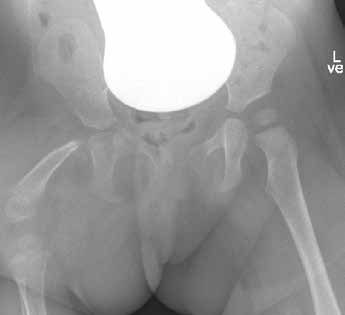

Die Patientin wird mit einem proximalen Femurdefekt rechts, Typ 2 A (Klassifikation n. Paley), geboren. Der Bewegungsstatus im Fußgelenk ist frei, im Kniegelenk erzeugt eine Insuffizienz des hinteren Kreuzbandes Instabilität. Es besteht ein Streckdefizit im Kniegelenk von 25°. In der Hüfte ist die Abduktion eingeschränkt, das Streckdefizit liegt nach der Neutral-Null-Methode bei 0°/45°/110° Ex/Flex, die Rotation ist frei. Eine Arthrographie im Juli 2013 zeigt einen fest im Acetabulum liegenden 8 mm kleinen Hüftkopf. Zu diesem Zeitpunkt ist eine OP nicht indiziert (Abb. 1a–c).